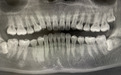

因为原本就害怕看牙,小六前前后后思考了几个月,终于下定决心挂了号来看智齿,医生给她拍了片子,然后看到了她的牙齿全貌。

两颗智齿在牙槽骨内横长着,属于埋伏阻生智齿,其中一颗还靠近下颌神经管;第三颗智齿虽然有“出头”的迹象,但是不在视线范围内。总结成一句话,这三颗牙,都不好拔。

1. 术前X线片,通过口腔CT确定伏牙在颌骨中的位置

这种情况你只有通过拍摄口腔全景片才能看清。你是不是也很好奇自己的智齿长什么样,要不要拔,好不好拔?

其实,无论现在的牙齿状况如何,建议都去拍一次牙片(口腔全景片)。这样不仅可以知道智齿到底有没有长出来,长啥样,也能全面了解口腔健康情况。